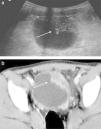

Se trata de un niño de 3 años y 5 meses de edad que acudió al Servicio de Urgencias por disuria, con cerca de 2 meses de evolución, que se fue agravando progresivamente, manifestando fiebre en los últimos días (temperatura máxima 38,1°C) acompañado de leucorrea. Junto con estos síntomas, manifestaba anorexia y una pérdida ponderal de cerca de 7% en el último mes. Los antecedentes personales y familiares eran irrelevantes. En el examen objetivo presentaba, en general, un buen estado, peso de 14,7kg, temperatura axilar de 36,4°C, presión arterial 105/70mmHg y frecuencia cardíaca de 100bpm, con mucosas coloradas e hidratadas, sin adenopatías palpables y con abdomen doloroso a la palpación en el hipogastrio, sin defensa. El resto del examen objetivo no presentaba alteraciones relevantes. Resultados del estudio analítico: hemoglobina 11,3g/dL (11,1-14,1); leucocitos 8.430/μL (5-15) con 3,4% eosinófilos; velocidad de sedimentación 33mm/1a h; funciones renal y hepática, normales, e ionograma sin alteraciones. Marcadores tumorales: alfafetoproteína y antígeno carcinoembrionario normales; enolasa específica de las neuronas aumentada (16,5ng/mL [valores de referencia < 12,5ng/mL]). Análisis de orina sin alteraciones y urocultivo negativo. Serologías: inmune a los virus de Epstein-Barr, de la varicela zóster, el herpes simple, el citomegalovirus y la rubéola. La ecografía mostraba una formación expansiva de la pared anterosuperior de la vejiga con cerca de 4,5×3,8×2,0cm, que indicaba un proceso infiltrativo, compatible con rabdomiosarcoma. Ante la sospecha de enfermedad oncológica, se realiza una tomografía axial computarizada, que confirma la lesión vesical, no siendo visibles otras alteraciones expansivas toracoabdominales, por lo que se le realiza una biopsia incisional (fig. 1). El estudio histológico revelaba infiltración eosinofílica de la pared vesical, característica en la CE (fig. 2). Se inició corticoterapia (metilprednisolona), observándose una reducción significativa de la lesión después de 3 semanas de tratamiento, completado hasta las 12 semanas. El seguimiento, a los dos años, no refleja enfermedad clínica y/o por imagen.

La CE es una enfermedad inflamatoria caracterizada por la infiltración de eosinófilos en las paredes de la vejiga. Aunque afecte a niños y adultos, es muy raro en aquellos, existiendo cerca de 30 casos1 referidos en la literatura desde 1960 (el primer caso fue descrito por Brown). Ocurre con mayor frecuencia en niños de sexo masculino y con edades superiores a los 6 años. La fisiopatología es incierta: aparentemente la lesión ocurre por la liberación de citocinas y agentes de quimiotaxia que dependen de los eosinófilos, liberación desencadenada por IgE. En el 29% de los casos se han relacionado los siguientes predisponentes: historia de enfermedad vesical, cirugía previa al aparato genitourinario, infecciones bacterianas y víricas, parasitosis, asma, enfermedades oncológicas, historia personal de alergias alimentarias (tomate, zanahoria) y a medicamentos (penicilina, sulfamidas)2,3. Los síntomas son inespecíficos y varían entre disuria, polaquiuria, hematuria y dolor suprapúbico, pudiendo mimetizarse en una infección urinaria. Analíticamente, la eosinofilia periférica surge en el 40-50% de los casos, siendo raro el aumento de las IgE4. El análisis de orina puede presentar hematuria y piuria, habiendo sido positivo el cultivo solo en el 20,5% de los casos5. Al nivel de las imágenes, las alteraciones pueden variar desde un espesamiento de la pared vesical a una formación vegetante, que sugiere un tumor, siendo el rabdomiosarcoma el principal diagnóstico diferencial en el niño6. El diagnóstico definitivo de la CE es histológico, caracterizado por un edema de la submucosa, con infiltración inflamatoria mixta con predominio eosinofílico.